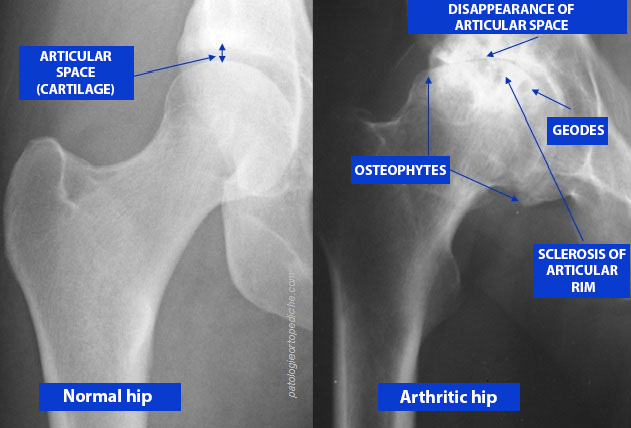

Csípőízületi porckopás (coxarthrosis)

A csípőízületi porcfelszínek elkopása – az ún. artrózis – igen gyakori betegség. Enyhe formájában csak kifejezett terhelés során jelentkezik mérsékelt csípőtáji fájdalom, azonban a súlyos kopás a járást is erősen megnehezíti, vagy akár járásképtelenséget is okozhat, az életminőséget jelentősen rontva.

A csípőízületi kopás kezdeti szakaszában jellemző a terhelésre jelentkező csípőtáji fájdalom, valamint a hosszabb pihenés utáni első lépések fájdalmassága, (un. indítási fájdalom) mely néhány lépés után “bejáródik”. Ilyenkor a csípőízületi porcfelszín felpuhulása, később annak felrostozódása figyelhető meg, mely a fokozatosan leváló kisebb rostok miatt az ízület izgalmi állapotát, gyulladását eredményezi; utóbbi felelős a fájdalom kialakulásáért.

A betegség korai szakaszában a cél az ízületi gyulladás csökkentése, a fájdalom megszüntetése, a kiváltó ok kezelése. A lehetőségek: